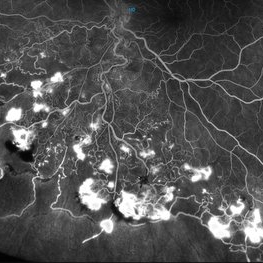

Nov 17 2025 by SHRADDHA RAJ SHRIVASTAVA

This left eye montage fundus fluorescein angiography (FFA) image of a 19 year old male with idiopathic retinal vasculitis, having skip vasculitic lesions predominantly involving retinal veins. There are areas of blocked fluorescence due to intraretinal hemorrhages, the involved veins have filling defects and occlusions, leading to formation of numerous collateral channels. The inflamed vessels also show perivascular fuzzy hyperfluorescent stain due to leakage of dye. We can also see multiple peripheral capillary non perfusion (CNP) areas, with a 'hot disc', suggestive of ongoing inflammation.

Photographer: Dr. Shraddha Raj Shrivastava

Imaging device: Nidek Mirante SLO/OCT (Confocal scanning/Spectral domain OCT)

Condition/keywords: FA late phase leakage, Fundus Fluorescein Angiography, idiopathic retinal vasculitis, optic disc leakage, VASCULITIS